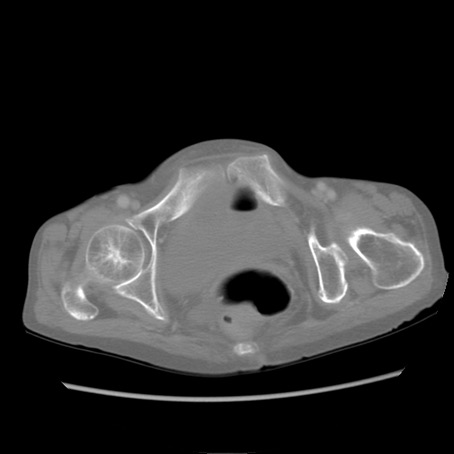

冠状断像

【症例】80歳代女性

【主訴】胸のつかえ感

【現病歴】約9時間前に食後から胸のつかえた感じあり、嘔吐あり、来院。

【既往歴】胃癌(全摘)、胆摘、虫垂炎

【身体所見】心窩部に圧痛あり、反跳痛なし。

【データ】WBC 5700、CRP 0.05